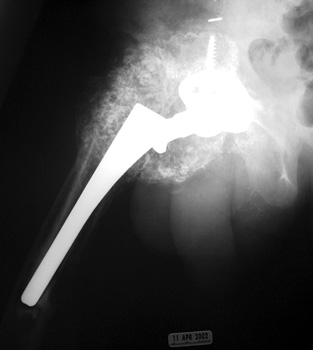

HETEROTOPIC BONE FORMATION adjacent to loose femoral component, plain film and CT